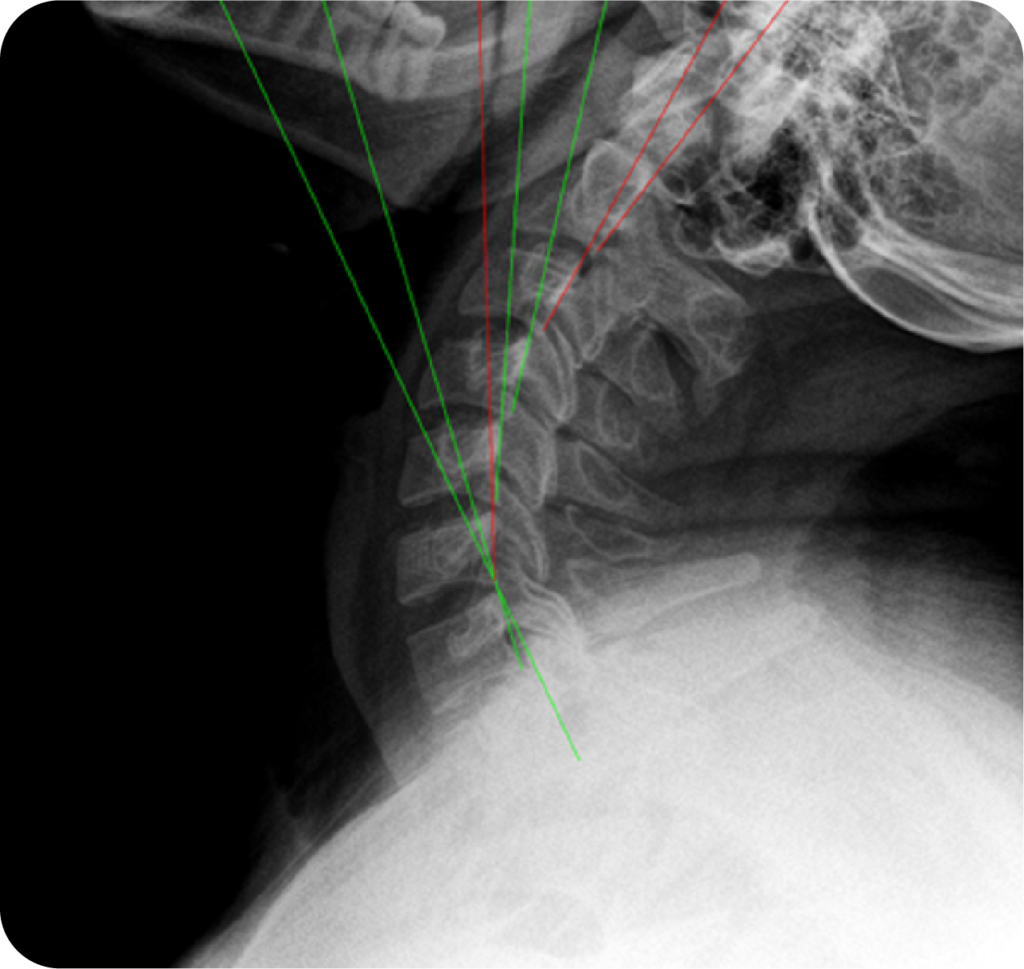

Digital X-Ray & PostureRay® Biomechanical Analysis

On-site digital radiography integrated with PostureRay® delivers precise biomechanical measurements of spinal alignment, motion, and structural deviation—providing objective data to identify injury, guide treatment, and document measurable correction.